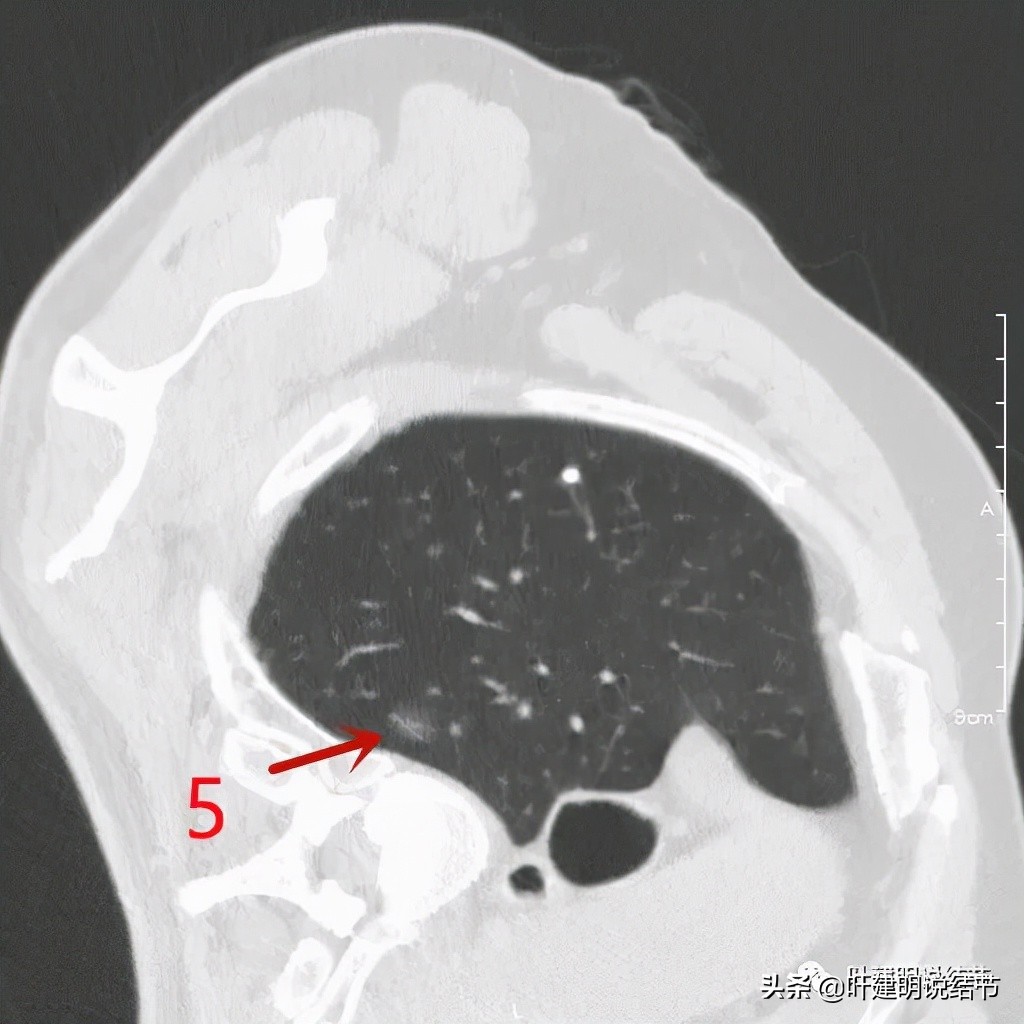

右侧病灶5:淡磨玻璃结节,大概会是原位癌,不能完全除外不典型增生或微浸润性腺癌。